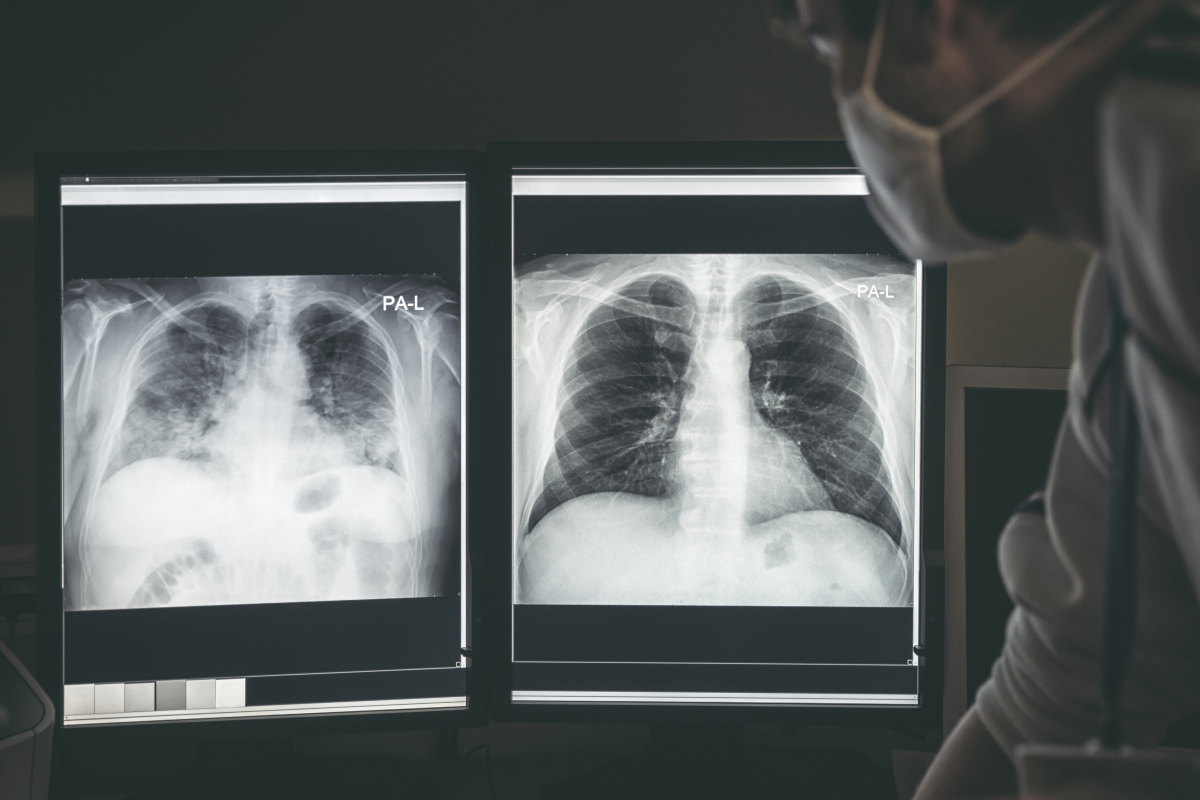

Zdjęcie rentgenowskie wykazało, że w lewym płucu chłopca znajduje się przedmiot. Utknęła tam... metalowa sprężynka. 8 marca w Narodowym Instytucie Chorób Układu Oddechowego przeprowadzona została operacja usunięcia ciała obcego. Zabieg się udał i przebiegł bez żadnych komplikacji. Teraz chłopiec potrzebuje czasu, aby jego wydolność oddechowa się poprawiła. Pulmonolog, czyli specjalista chorób układu oddechowego, zamieścił na Instagramie krótkie nagranie. Widzimy na nim zdjęcie rentgenowskie płuc chłopca (widzicie sprężynkę?) i moment z zabiegu, kiedy ciało obce zostało wyciągnięte. Lekarz przestrzega, aby nigdy nie bagatelizować objawów. Pamiętajcie również, aby pilnować najmłodszych członków rodziny. Mogą oni połknąć drobne przedmioty w swoim zasięgu!